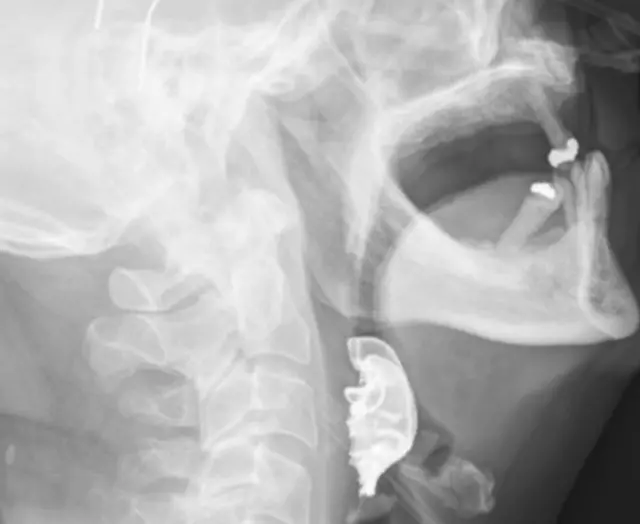

Hasta 2 gün sonra aynı şikayetle geri dönünce, doktorlar boğazını ve gırtlağını inceledi. İnceleme sonucu ses tellerinin üzerine yarım yuvarlak bir nesne olduğu fark edildi.

Hasta bu noktada, doktorlara 3 takma dişten oluşan protezini ameliyat sırasında kaybettiğini söyledi.